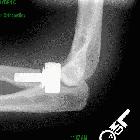

Elbow arthroplasties are an increasingly common joint replacement, most often used for treatment of late stage rheumatoid arthritis, but which may also be used as a treatment for late stage osteoarthritis or complex fractures of the proximal radius, proximal ulna, or distal humerus.

- total elbow replacement

- meant to restore the hinge (ginglymoid) function of the ulnotrochlear component of the elbow joint

- semiconstrained ("sloppy hinge"): more common, permits mild varus and valgus motion

Imaging evaluation usually requires AP and lateral views, and focuses on looking for loosening or periprosthetic fracture:

- periprosthetic lucency

- periprosthetic osteolysis (micromotion or particle disease)